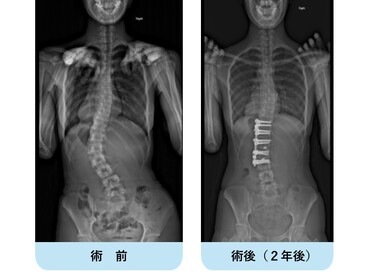

腰椎が曲がっているタイプの特発性側弯症です。

前方からの脊柱側弯矯正固定術で真っ直ぐになっています。

比較的短い範囲の矯正固定術で可動椎間を多く残せることがメリットです。